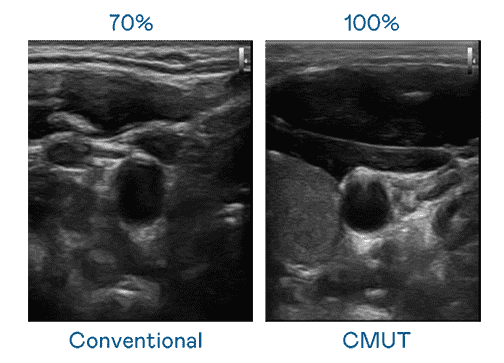

CMUT 技术是一种用电容式微机电元件来产生超音波讯号的技术。。。。与传统 PZT 压电式技术相比,,CMUT 频宽增加 30%,,更宽频的超音波讯号让影像解析度大幅提升,,,是实现高影像品质医疗超音波扫描、、促进精准医疗发展的关键技术。。。。

大频宽带来超清晰影像

超音波影像的解析度高低,,,首先取决于探头能发出的讯号频宽。。。NG大舞台 CMUT 可提供高清晰的超音波讯号,,,提供高频宽、、、、高灵敏度、、、影像纹理细节更高的超音波影像,,协助医护人员缩短影像判读时间及利用精准的医疗影像进行诊断。。。